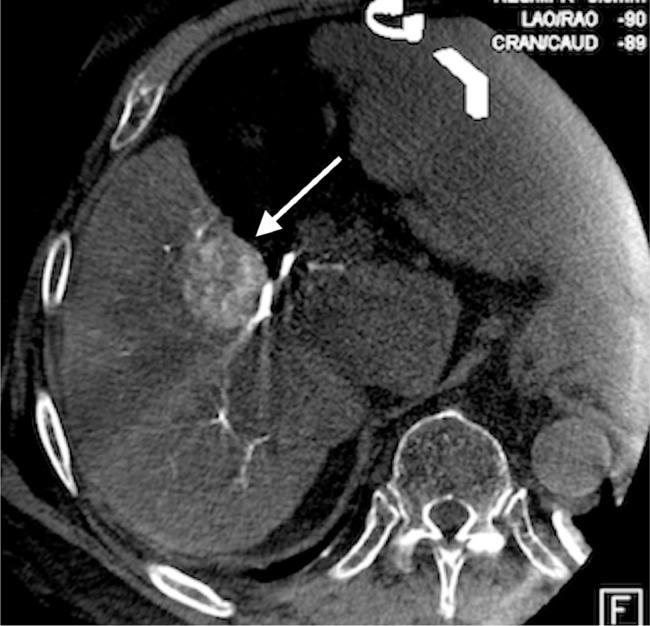

Severe reactions to modern iodinated contrasts are uncommon. Breakthrough reactions in the setting of pretreatment with corticosteroids are even rarer. Patients with a history of these refractory reactions can create challenging situations in the diagnostic and therapeutic process. Here, we present a case of an 83-year-old male with hepatocellular carcinoma and a history of multiple severe reactions to iodinated contrast. The patient required a transarterial chemoembolization but the conventional technique was unavailable due to the allergy. Gadolinium-based contrast was substituted and used in conjunction with C-arm CT and a percutaneous ethanol injection to treat the tumor. After nearly 3 years, there is no evidence of residual or recurrent hepatocellular carcinoma.